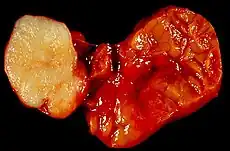

| Parotid gland tumour | |

Salivary gland tumours, also known as mucous gland adenomas[1] or neoplasms, are tumours that form in the tissues of salivary glands. The salivary glands are classified as major or minor. The major salivary glands consist of the parotid, submandibular, and sublingual glands. The minor salivary glands consist of 800 to 1000 small mucus-secreting glands located throughout the lining of the oral cavity.[2] Patients with these types of tumours may be asymptomatic.[1]

Little is known about the total incidence of salivary gland tumours as most benign tumours go unrecorded in national cancer registries.[3] The majority of salivary tumours are benign (65-70%).[4] Within the parotid gland 75 - 80% of tumours are benign. Around 50% of the tumours found in the submandibular glands are benign. Sublingual gland tumours are very rare but if present, they are most likely to be malignant.[4][19] Saku et al. in 1997 [20] and Venturi [21][22] in 2021, reported the causal role for ionizing radiation in salivary gland tumorigenesis, particularly for mucoepidermoid carcinoma.